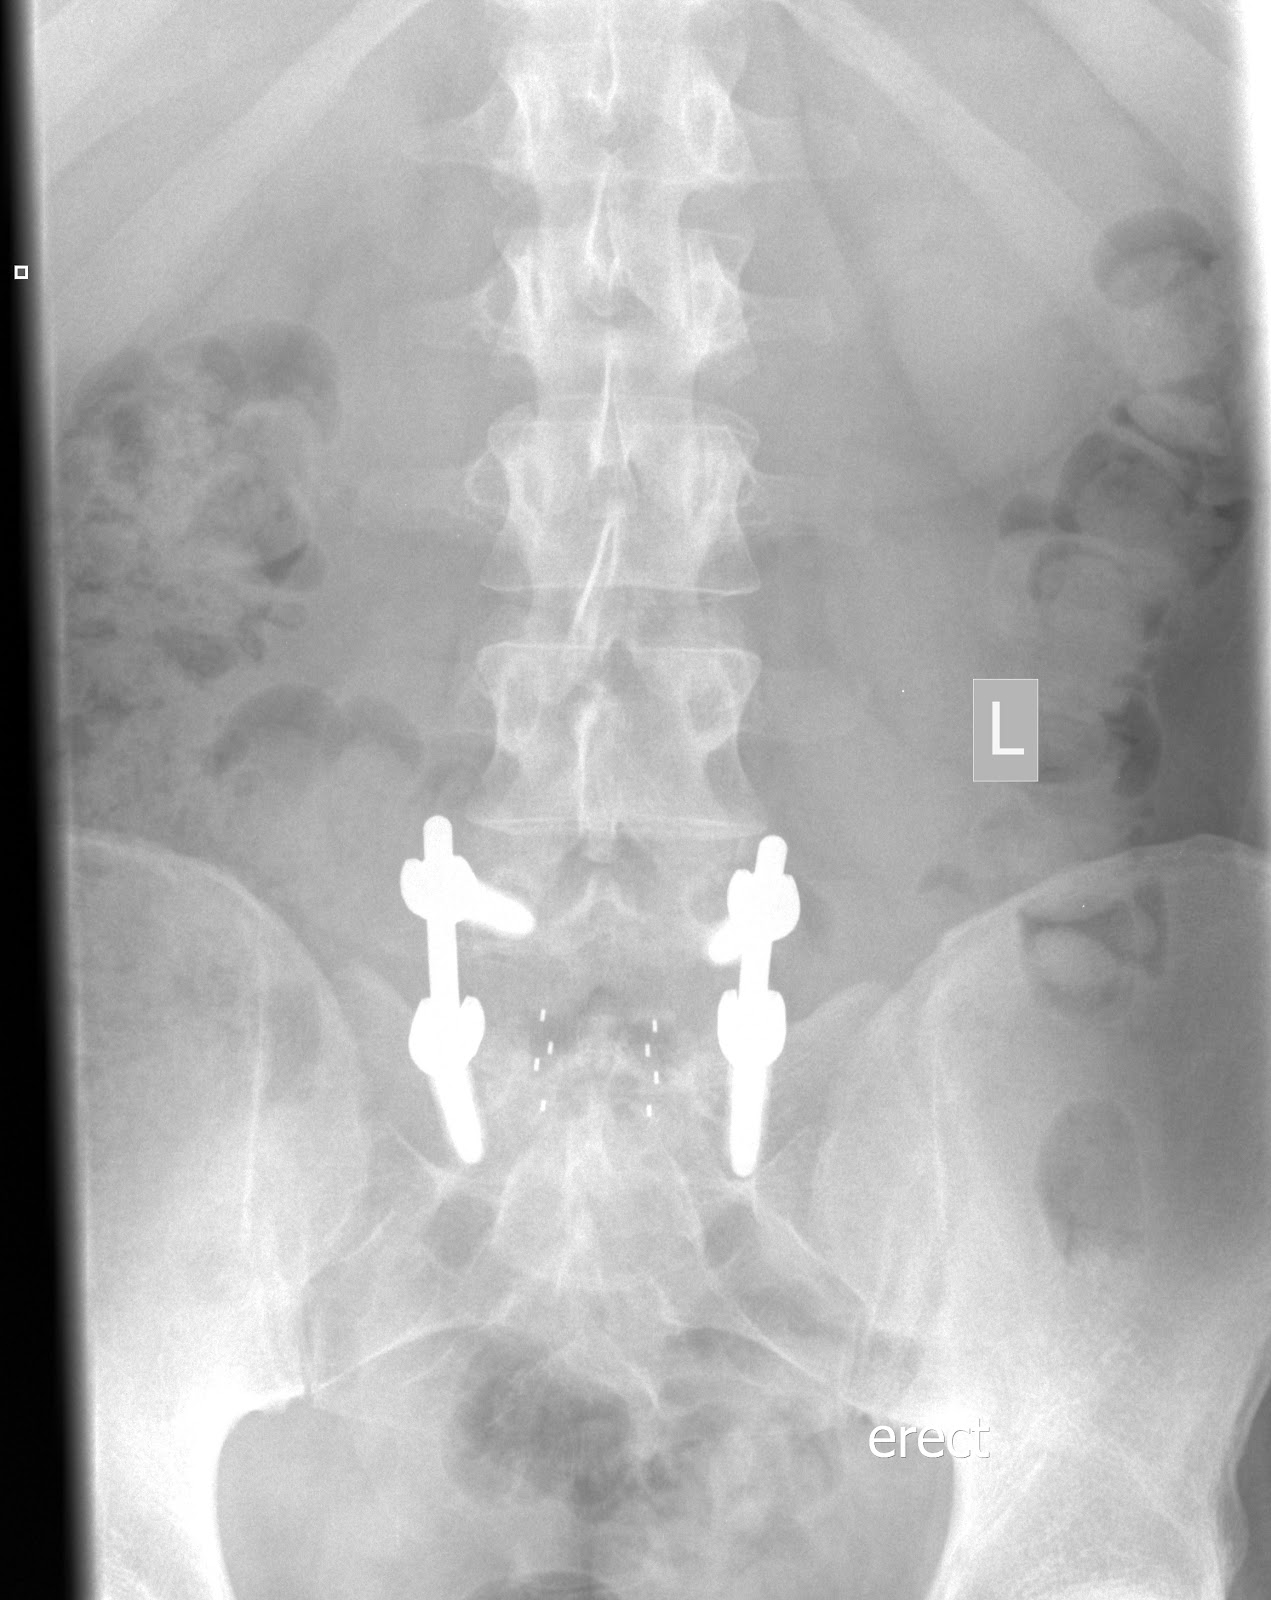

Recovery From Spinal Spacer Surgery. Web the interspinous spacers create space at the back of your spinal column to open additional room for your spinal nerves. Less discomfort and a decreased need for pain medications. Avoid wearing jewelry on your surgery date. Web avoid bathing with certain soaps. Once it is inserted between two vertebrae, the spacer’s arms open around the spinous process of the lumbar spine to lock the device into place. Web the interspinous spacer procedure involves a minimally invasive titanium spacer implanted through a tiny tube via a small incision in the lower back. Web for some patients, though, the risk of these surgical procedures makes it more challenging to effectively treat the condition and recover following the. Web an isd implantation also uses a midline approach in between the spinous process and leaves inside a foreign body (the interspinous spacer). Web will begin 3 weeks after surgery (3x a week for 4 weeks). What to expect during your interspinous spinal.

What to expect during your interspinous spinal. Web an isd implantation also uses a midline approach in between the spinous process and leaves inside a foreign body (the interspinous spacer). Less discomfort and a decreased need for pain medications. Web the interspinous spacer procedure involves a minimally invasive titanium spacer implanted through a tiny tube via a small incision in the lower back. Web for some patients, though, the risk of these surgical procedures makes it more challenging to effectively treat the condition and recover following the. Web avoid bathing with certain soaps. Web will begin 3 weeks after surgery (3x a week for 4 weeks). Web the interspinous spacers create space at the back of your spinal column to open additional room for your spinal nerves. Once it is inserted between two vertebrae, the spacer’s arms open around the spinous process of the lumbar spine to lock the device into place. Avoid wearing jewelry on your surgery date.

Recovery From Spinal Spacer Surgery Web will begin 3 weeks after surgery (3x a week for 4 weeks). Web the interspinous spacer procedure involves a minimally invasive titanium spacer implanted through a tiny tube via a small incision in the lower back. Avoid wearing jewelry on your surgery date. What to expect during your interspinous spinal. Web avoid bathing with certain soaps. Web for some patients, though, the risk of these surgical procedures makes it more challenging to effectively treat the condition and recover following the. Once it is inserted between two vertebrae, the spacer’s arms open around the spinous process of the lumbar spine to lock the device into place. Web will begin 3 weeks after surgery (3x a week for 4 weeks). Web an isd implantation also uses a midline approach in between the spinous process and leaves inside a foreign body (the interspinous spacer). Web the interspinous spacers create space at the back of your spinal column to open additional room for your spinal nerves. Less discomfort and a decreased need for pain medications.